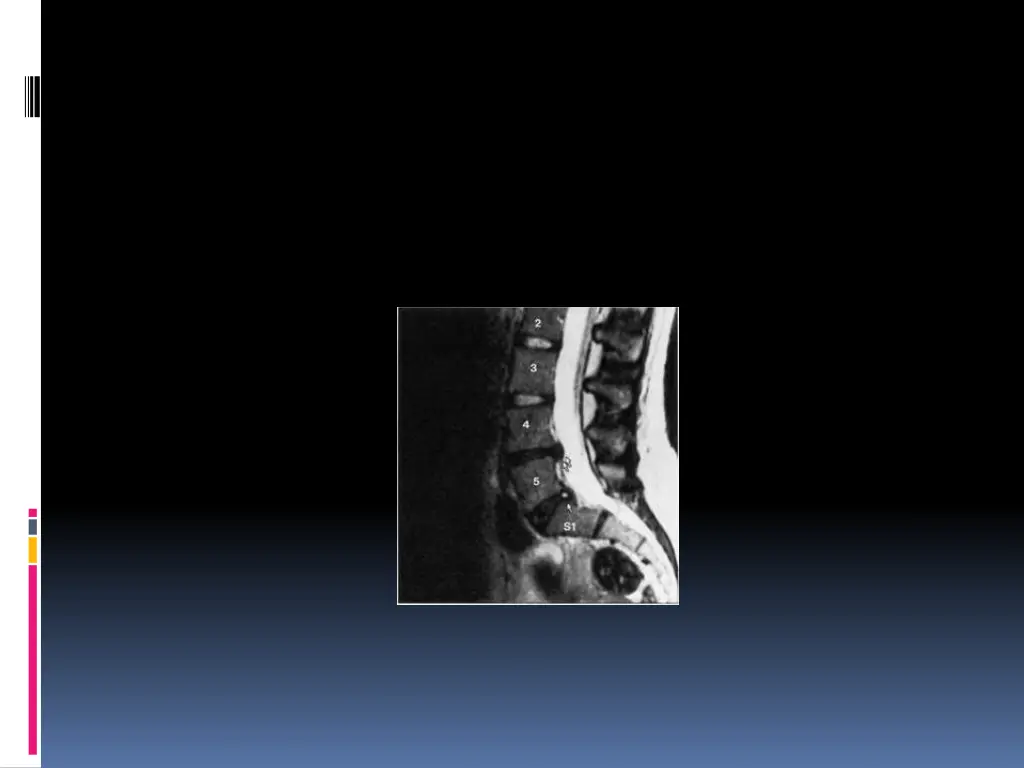

SCANNER: Visualise la hernie, sa situation, son importance et la surface utile du canal rachidien. Coupes millim triques sus et sous-jacentes l espace discal v rifient l ventualit d une migration et son importance L IRM: Si la TDM ne d c le pas la hernie Si r cidive apr s CHX My lographie ou saccoradiculographie EMG